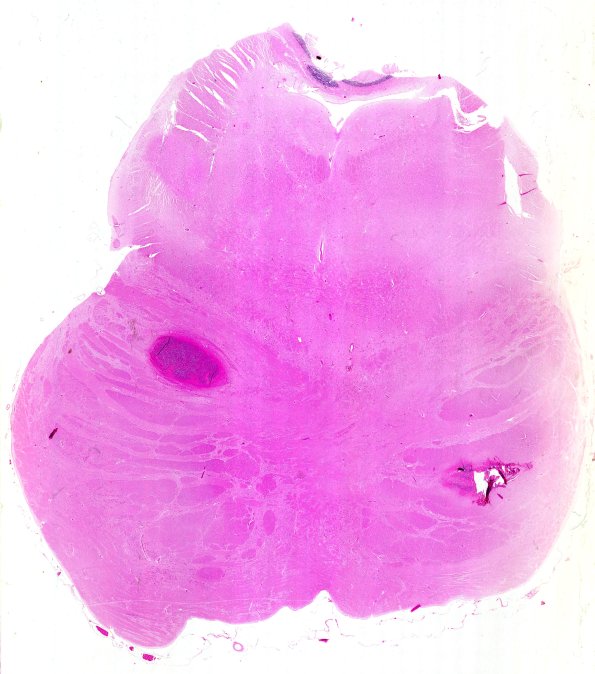

A whole mount of the pons showing small lesions in the basis pontis. (H&E)